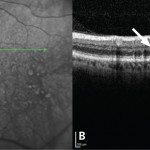

Diagnosi di RAP (retinal angiomatous proliferation): un approccio multi-imaging